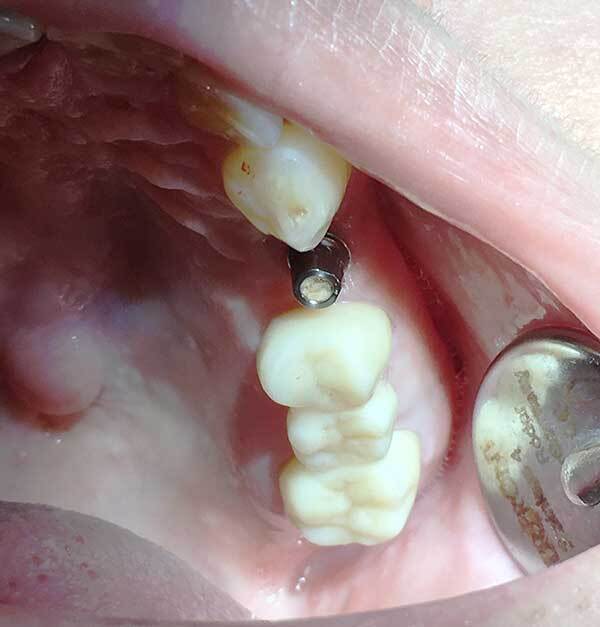

インプラント

歯をなくした部分に人工の歯を埋め込む治療です。差し歯や入れ歯とは異なり元の歯と同じように使えるというのがメリットです。

当院の特徴 「医師が行うインプラント治療」

ダブルライセンスドクターが施術当クリニックではダブルライセンスドクター(医師免許と歯科医師免許を持つ医師)がきちんとした精査を行い施術いたします。全身状態を精査したうえでオペを行います。全身疾患をお持ちの方も安心して治療を受けることができます。

料金は成功報酬

歯が入って、咬めることを確認したのちに料金が発生いたします。料金に不安の方も納得いただける料金設定となっています。

CT完備で安心のオペ

当院はCTを導入しており、骨欠損などの情報を把握したうえでOpeを行います。

最大限の安全を配慮したうえでオペを行います。歯科医では診断が困難であろう症例も医師としての目線でCT画像を読影いたします。